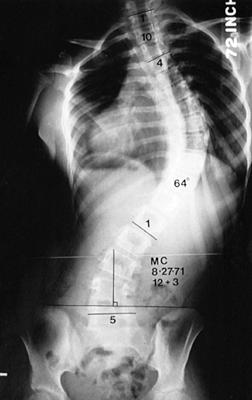

reported the long-term results of the Twin Cities Scoliosis Center’s

centered over the sacrum (Fig. 156.1, Fig. 156.2, Fig. 156.3, Fig. 156.4 and Fig. 156.5).

The lowest level of the fusion is established by drawing a line

this line is called the stable vertebra (Fig. 156.6). Ending the fusion at the stable vertebra gives uniformly good results.

Figure 156.2. Type II curve. The center sacral line has been created. The stable vertebra is T-12.